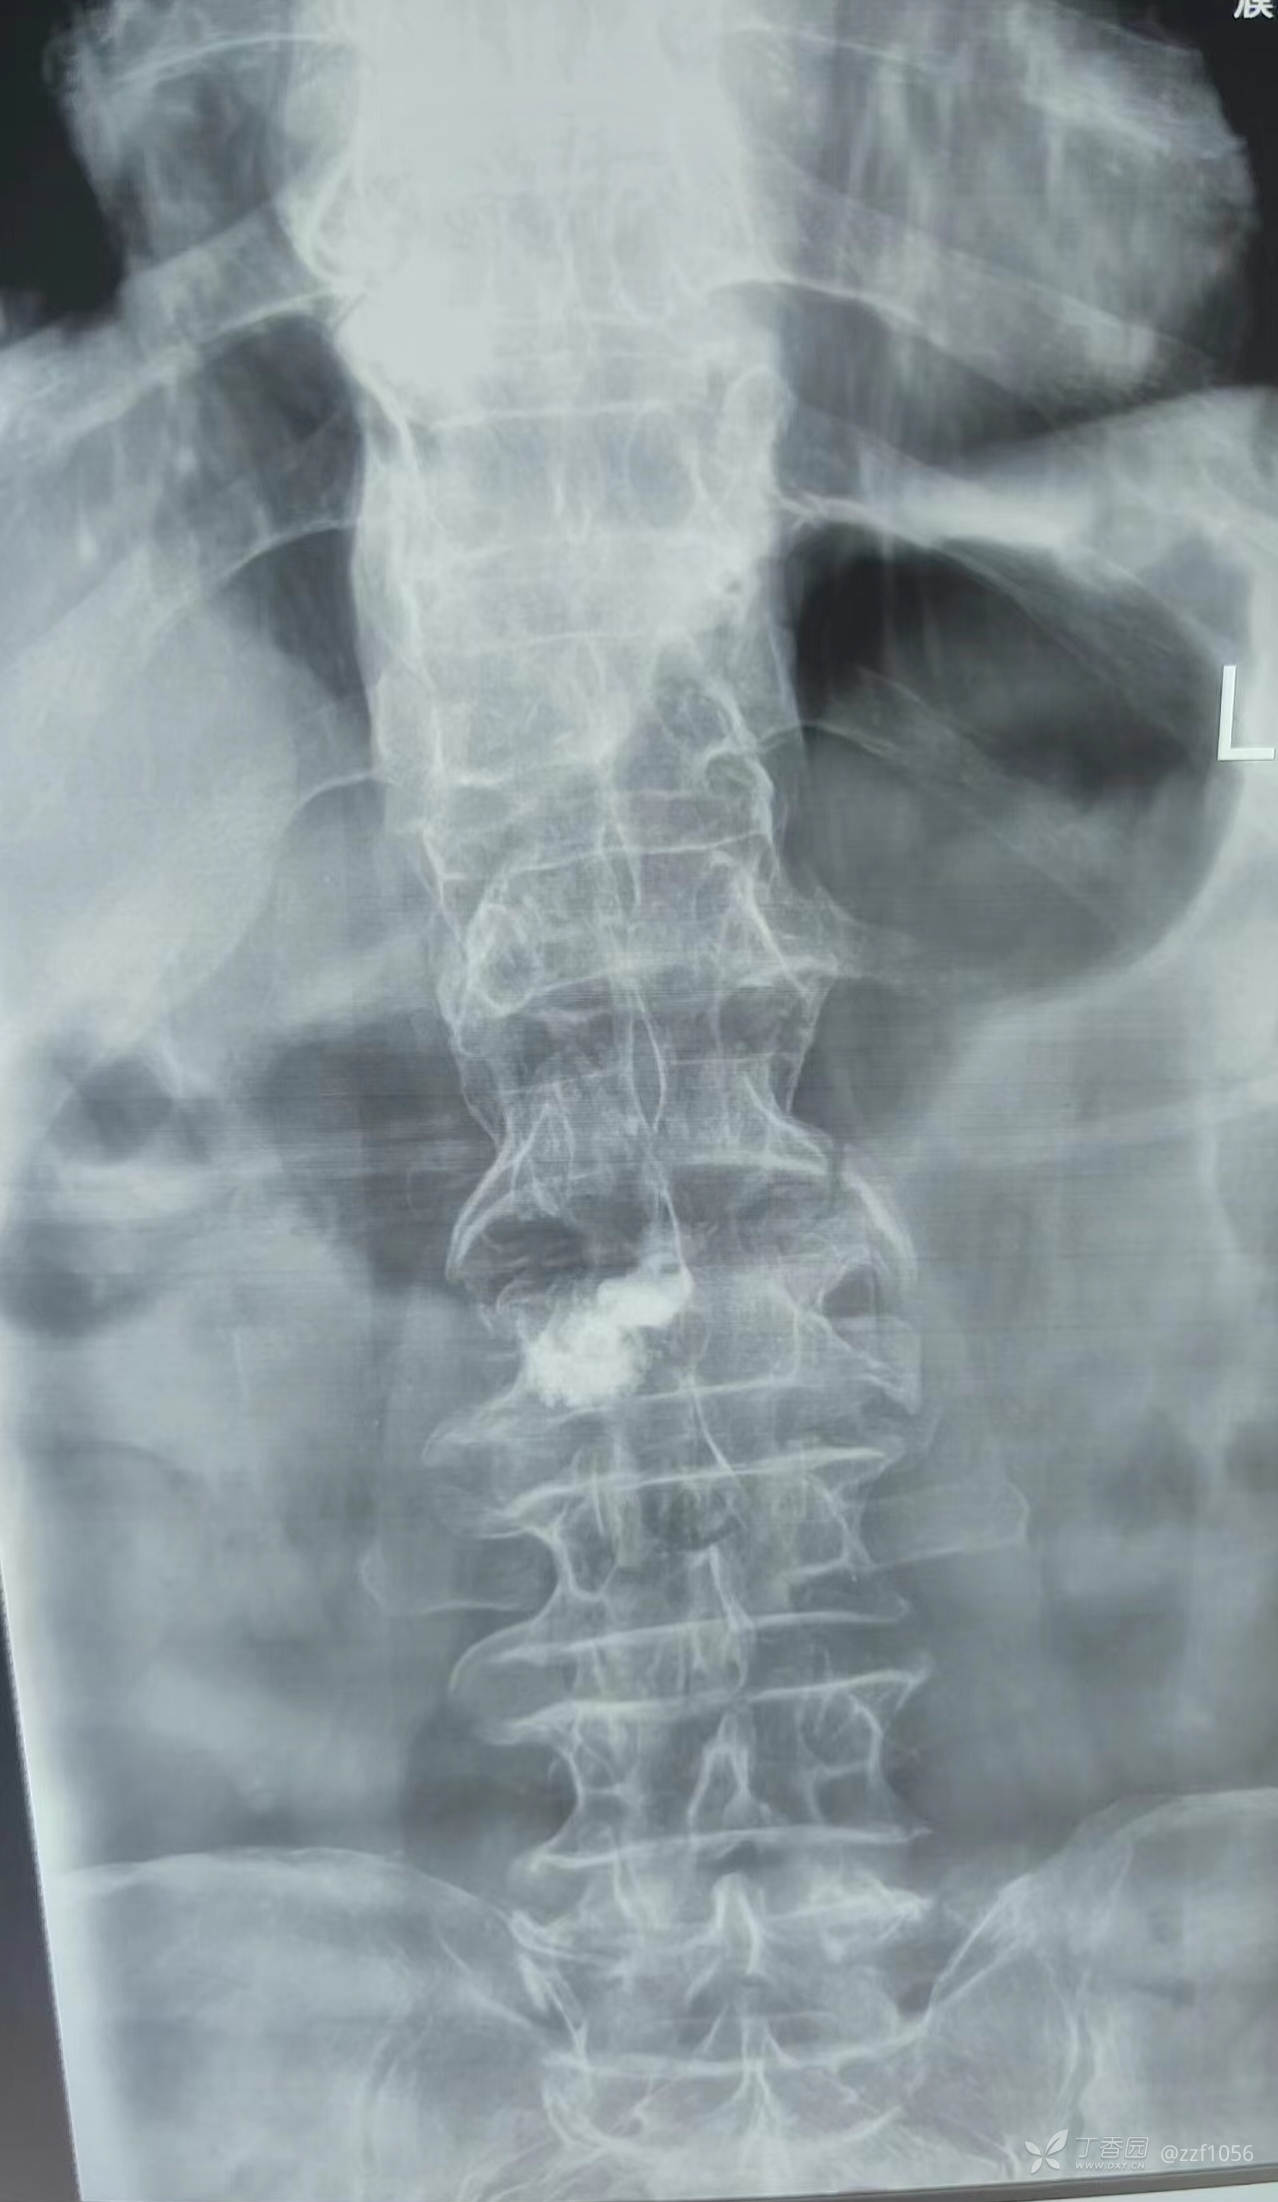

病例一(非我病例,单侧穿刺)

患者老年男性75岁,摔伤后腰痛大致20天才去医院就诊,甲医院完善CT及相关检查后实施L2椎体成形术,据术者说注入骨水泥后患者明显疼痛缓解,术后好转出院,回家下床后仍感觉腰痛不适,遂往乙医院就诊,磁共振后发现此椎体上一节段也有水肿信号,考虑骨折,再次行PVP,术后疼痛消失,现术后二十天已自行解除腰封,活动可。

病例二(非我病例,单侧穿刺)

患者老年男性,85岁

第一次甲医院术后